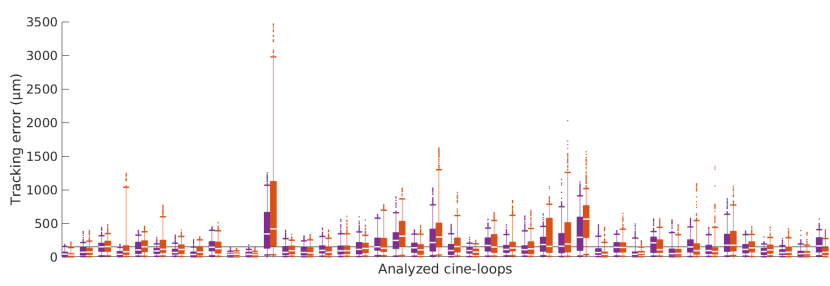

The motion was successfully extracted from all the analyzed cine-loops. The quantitative evaluation of the proposed DBM framework, showing the mean absolute () difference between the trajectories resulting from the manual reference annotations and those resulting from the method, is presented in Table 3, together with the comparison against the previously introduced KBM method. Overall, the temporal trajectories resulting from the DBM method demonstrated a good similarity with the manual reference annotations, as displayed in Figure 5c. It was also observed that the DBM method performed quite robustly, as opposed to the KBM method, which in some cases failed to capture the exact tissue motion due to progressive drift or sudden jumps to another target point. This is reflected by the Figure 6, where outliers are more numerous in the case of the KBM method.

The very nature of the DBM framework enabled for the extraction of a dense motion field . Several dynamic patterns, corresponding to different participants, are displayed in Figure 7. Although a quantitative analysis of the tracking accuracy was only performed in three local points per cine-loop, as described above, a qualitative assessment of the motion homogeneity can be obtained from these 2D fields.

The collaboration of all the points allowed for improved robustness. The spatial consistency of the motion was implicitly exploited within the front propagation step (Eq. 2), since the global optimum was preferred over a series of independent best matches, thus reducing the risk of individual tracking errors. To phrase it differently, the set of conditions ruling the behaviour between neighboring points could successfully maintain the cohesion of the mesh and prevent sudden jumps or cumulative drift errors. On the other hand, the mesh was flexible enough for the points to follow the motion of the tissues over time. This phenomenon is illustrated in Figure 5c. At this point, it is useful to differentiate accuracy and robustness. While accuracy describes the ability of a method to yield results close to the ground truth, robustness represents the capacity of a method to avoid failure and provide an exploitable result. In the present situation, it is unlikely that the DBM method could have a positive impact on the tracking accuracy per se, however the robustness was improved. Moreover, it should be noted that the combinatorial analysis, solved by means of dynamic programming, also enabled a simultaneous motion computation for a large collection of points in a rather limited time due to the intrinsic reduction of the solution space.